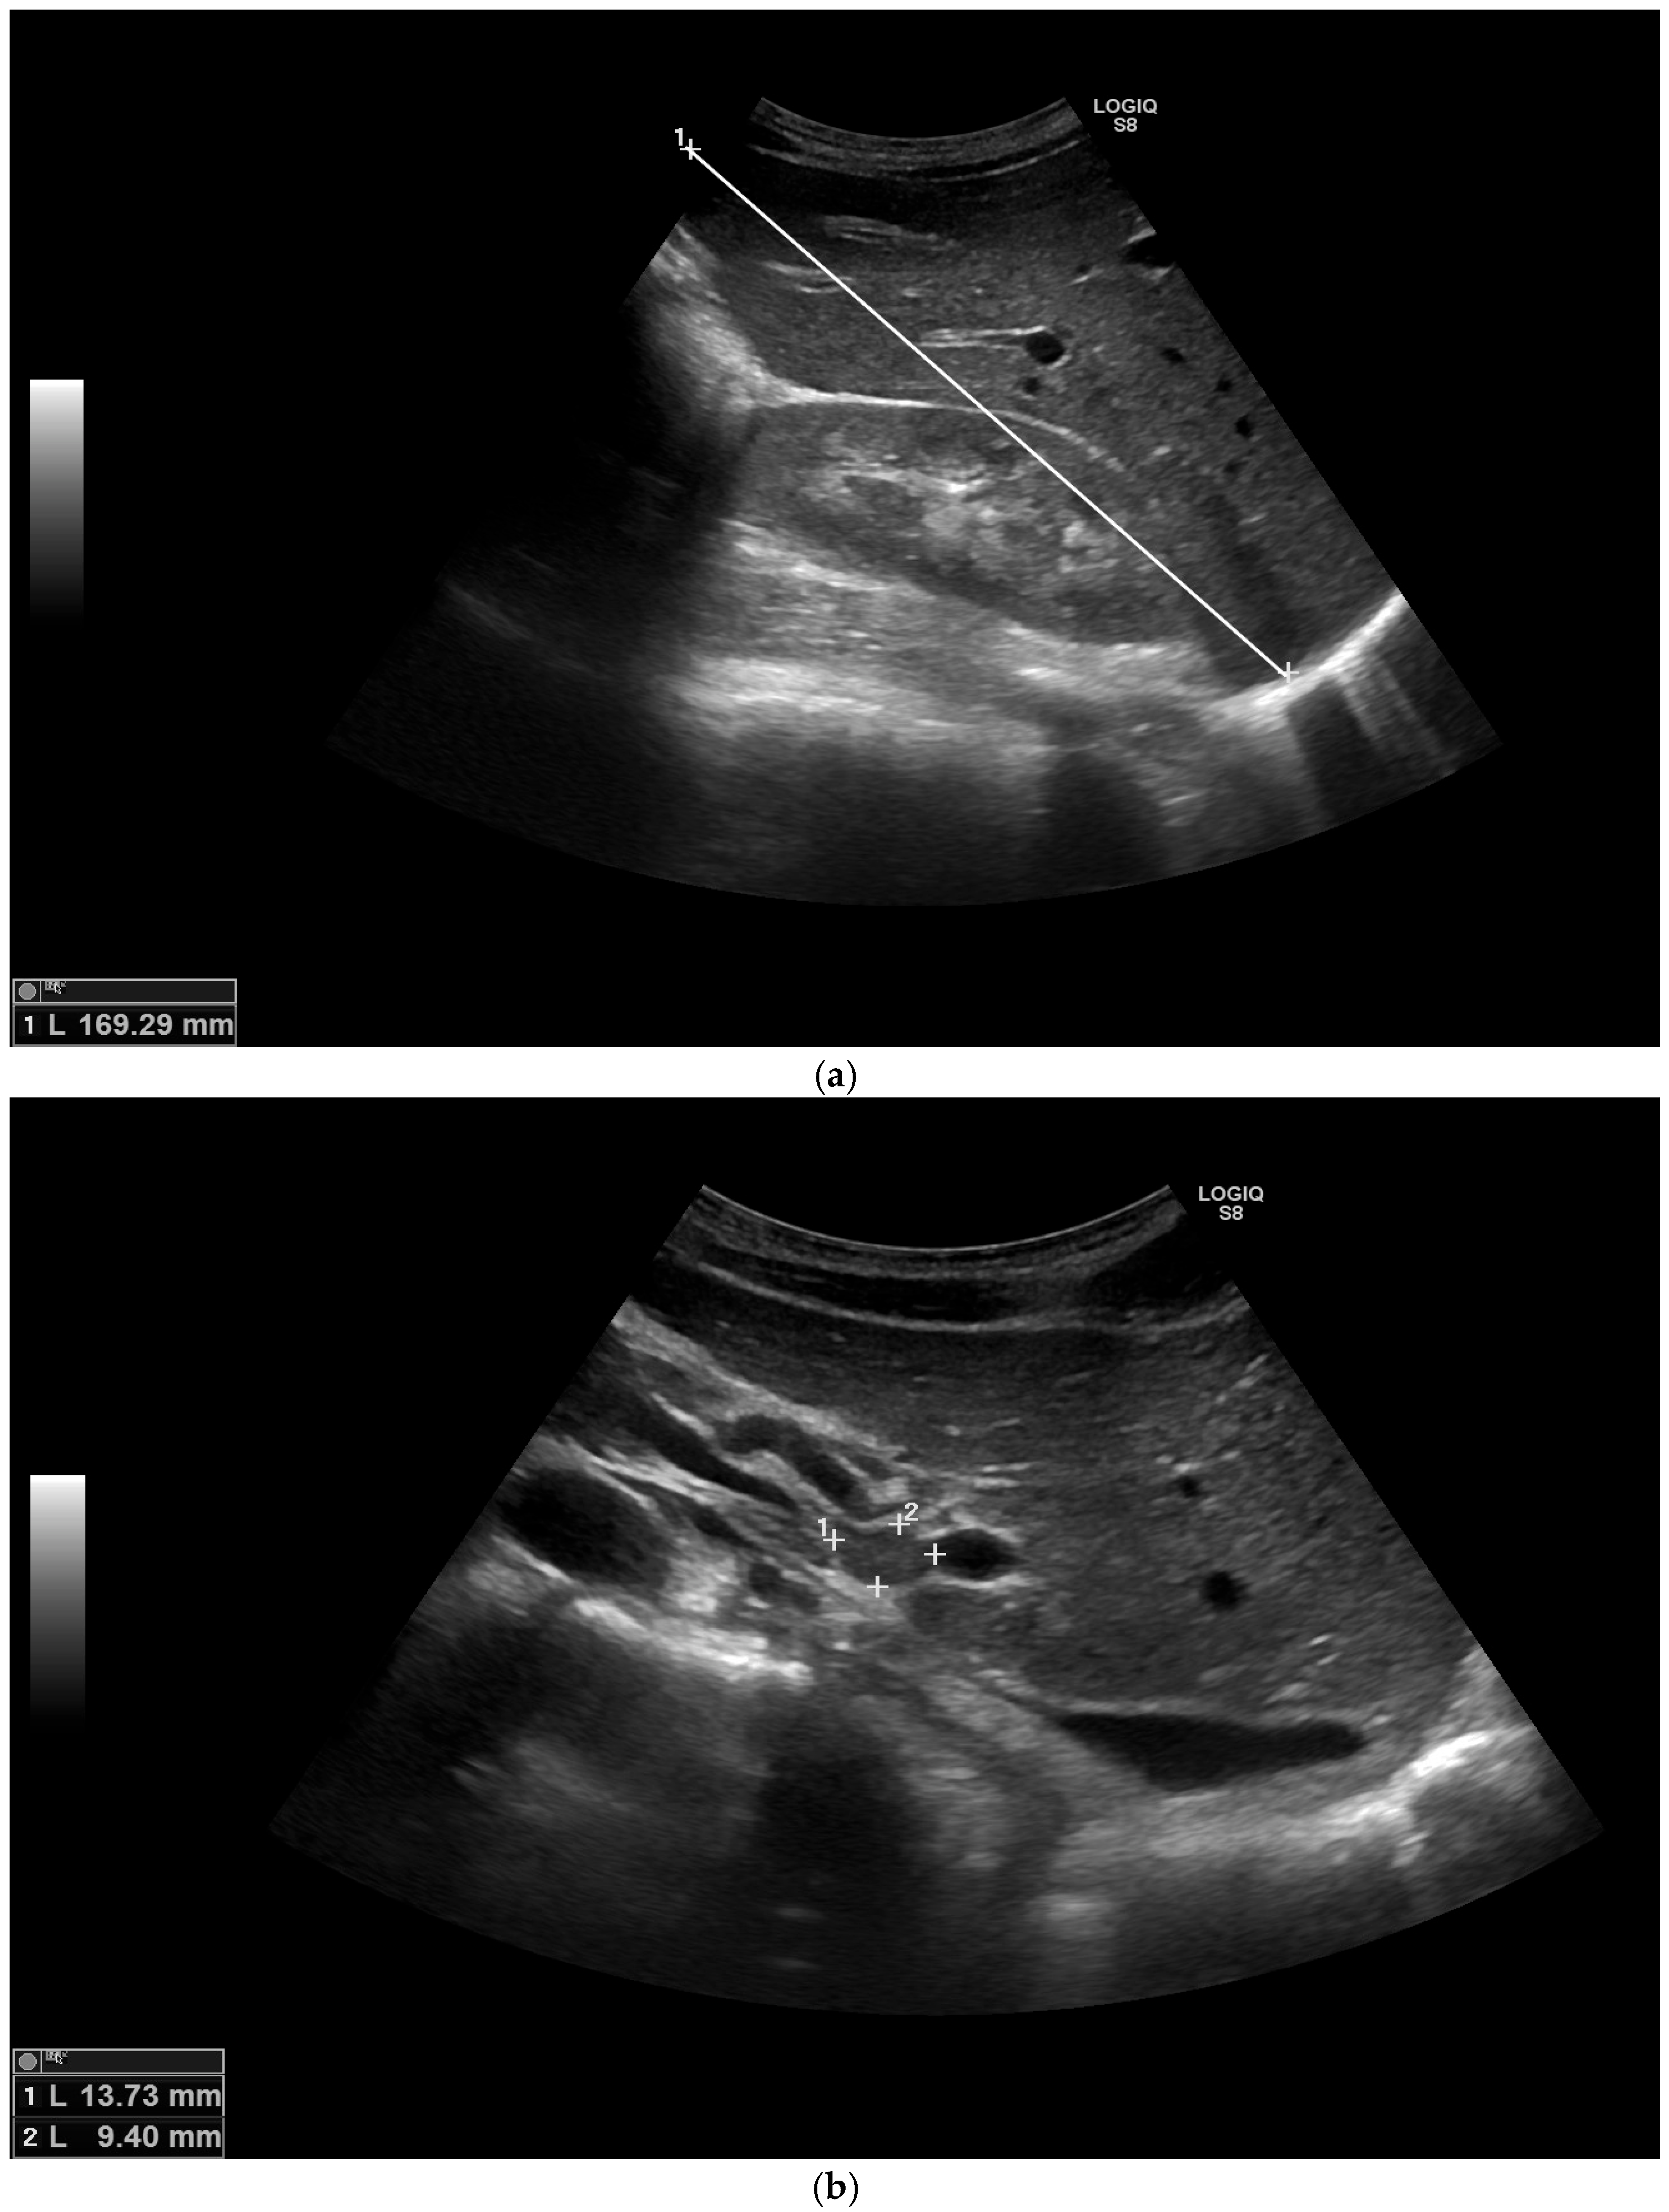

2. Case Report